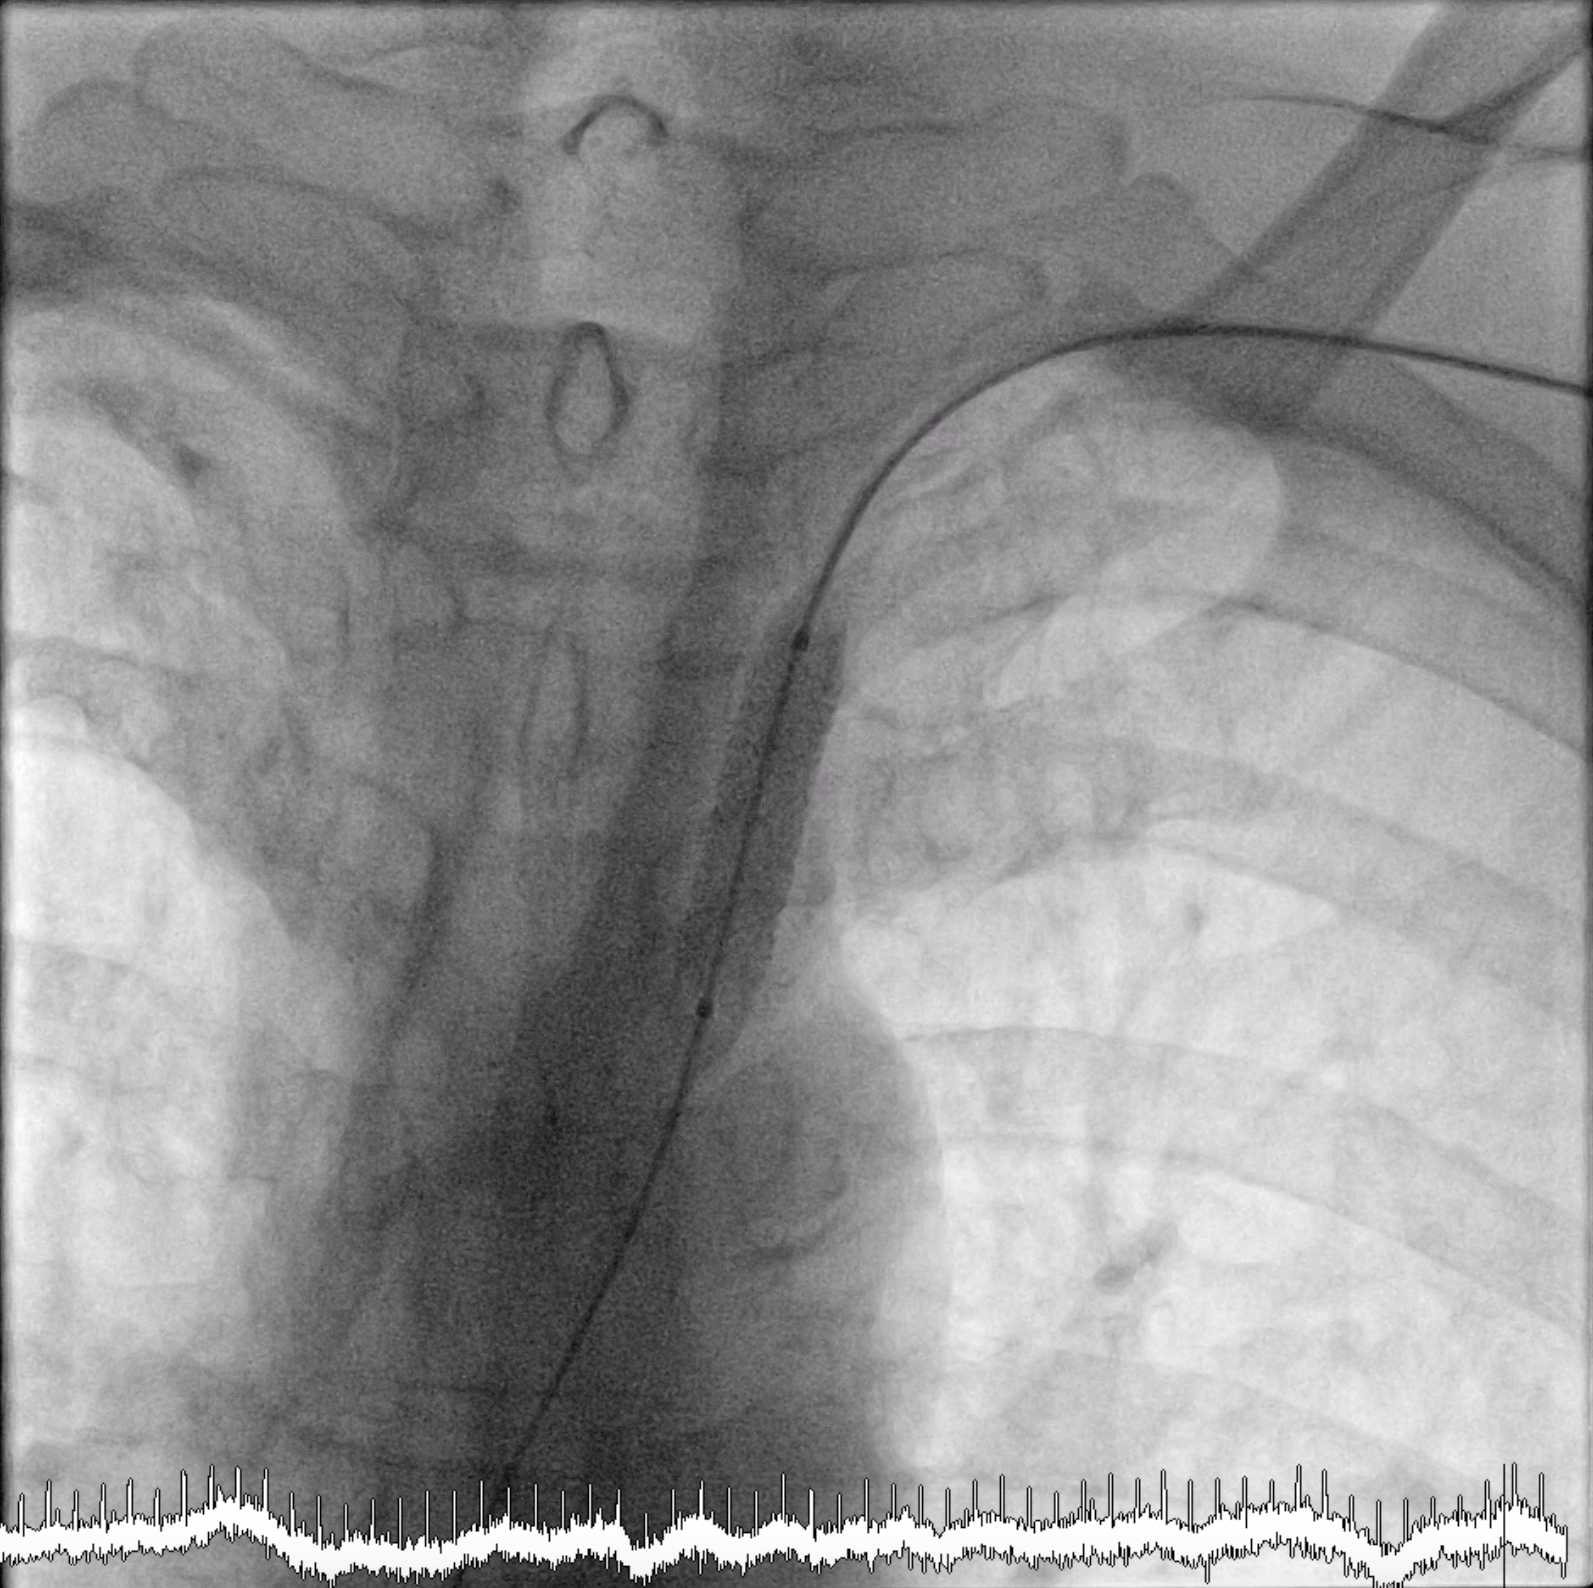

After we performed cine-angiography of the left subclavian artery using AP view, we drew the upper and lower border of the stenosis location with permanent marker on the machine¡¯s screen. We decided not to use a guiding catheter to intervene the left subclavian stenosis. Using JR 4.0 diagnostic catheter, we inserted 0.035¡± PTFE J tip guide wire 150 cm into the left subclavian artery, crossed the lesion, and secured distally into the aorta.We pulled out the JR 4.0 diagnostic catheter, then we delivered a MustangTM Balloon Dilatation Catheter (Boston Scientific) 5.0 x 40 mm into the lesion. We positioned the Mustang balloon according to the ¡®mark¡¯ that we made in the screen, then inflated it.After pre-dilating with the balloon, next we delivered ExpressTM Vascular LD Stent (Boston Scientific) 8.0 x 27 mm into the lesion (according to the ¡®mark¡¯) and deployed the stent. After that, we advanced the balloon stent about 3-4 mm further and post-dilated the stent.The final result was good with no residual stenosis and no dissection.